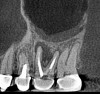

Surveying pulpal anatomy before initiating treatment is another area in which CBCT can benefit a trained operator. Understanding the internal anatomy of the root canal system can help in treatment planning a nonsurgical case, as well as a microsurgical case, to avoid procedural mishaps. CBCT can also facilitate the conservation of tooth and root structure.For instance, knowing whether a maxillary molar has a second mesiobuccal (MB) canal can help the practitioner avoid troughing or removing precious dentin when there is no MB2 canal. In addition, more accurately locating the MB2 canal when it is visible on CBCT also assists in conserving tooth structure. The same holds true for a possible lingual canal or additional canal(s) in a mandibular incisor (Figure 9) or bicuspid.

Fig 9. 3D CBCT image of mandibular incisors with two canals.

Figure 9